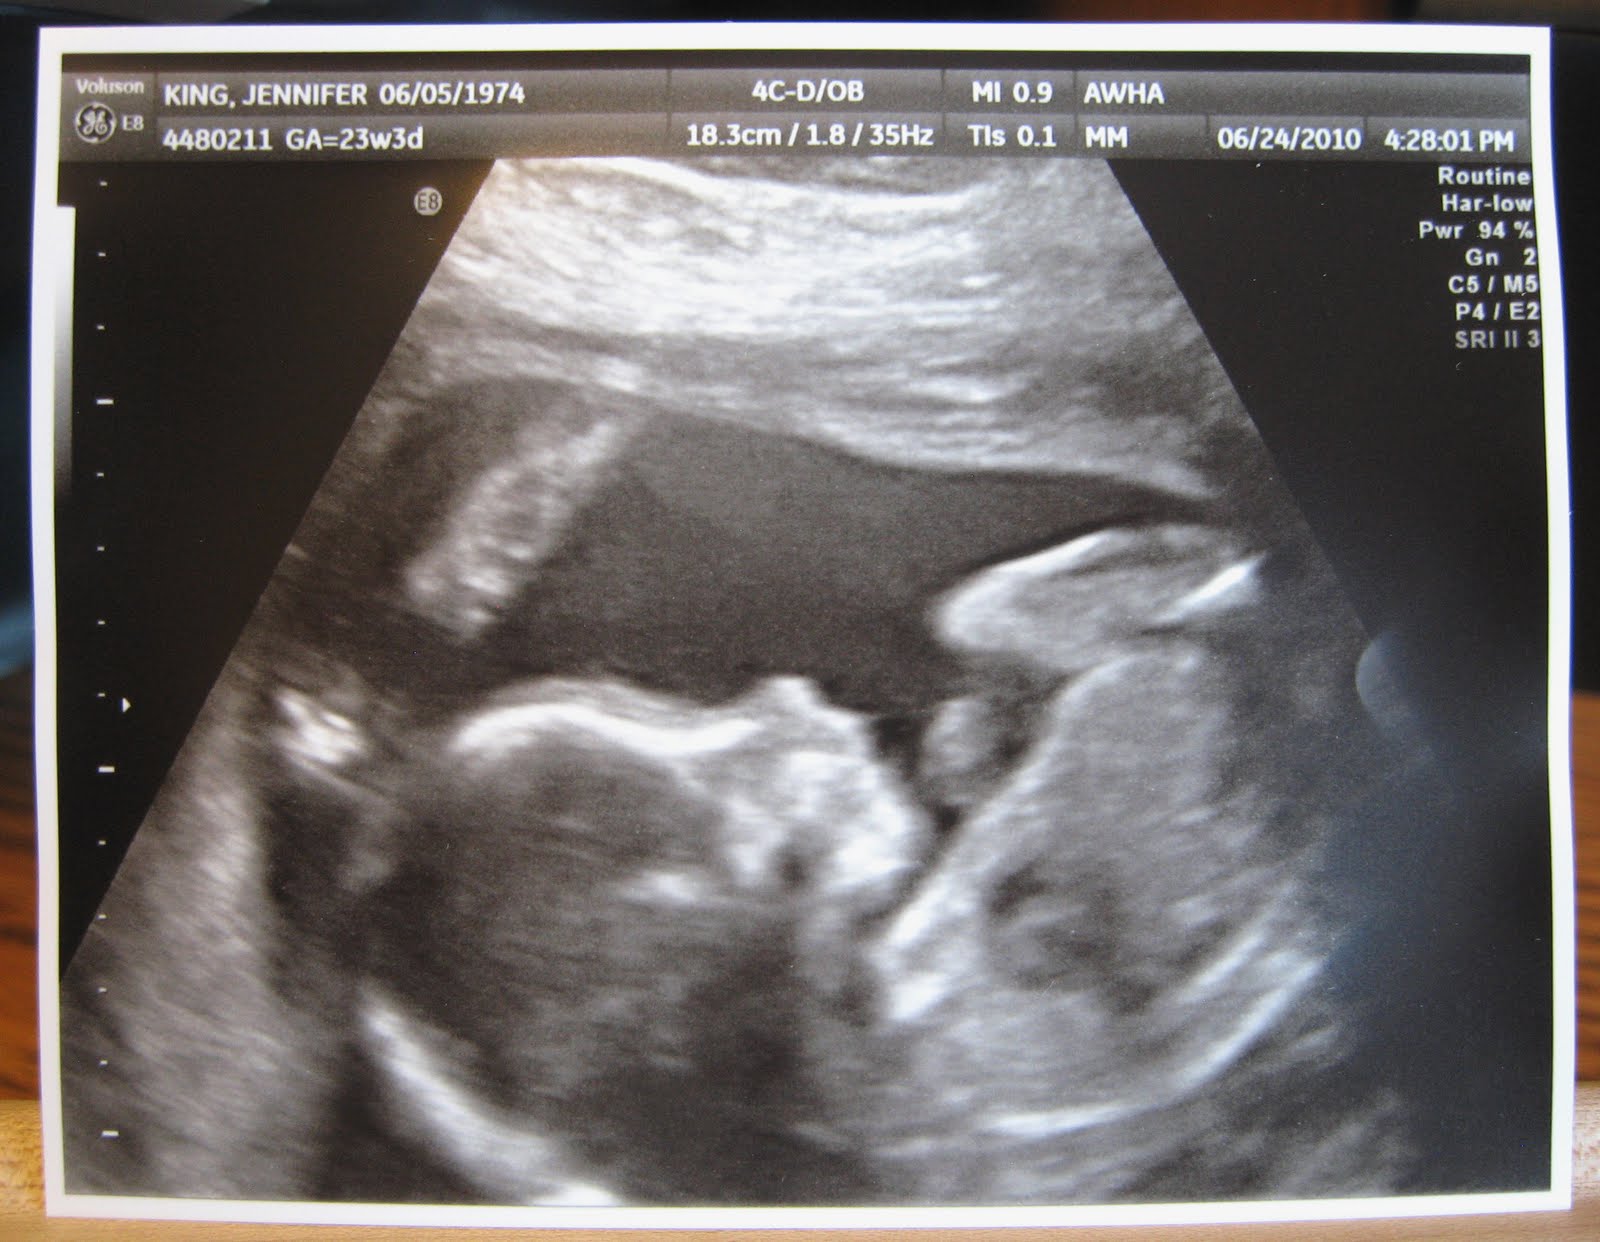

- К началу 25 недели гестации уже полностью завершено формирование половых органов (у девочек — матка, влагалище и фаллопиевы трубы, у мальчиков — половой член и мошонка.) На фото УЗИ, которое на этом сроке назначается только при наличии медицинских показаний, уже можно точно определить пол будущего ребенка.

УЗИ на 24 неделе беременности проводится только при наличии медицинских показаний. По плану это исследование осуществляется 2 неделями ранее. Внеплановое УЗИ назначается при поздней постановке будущей роженицы на учет или подозрениях в нарушении развития плода. Обязательные виды исследования на этом сроке — общий анализ крови и мочи. Кроме того, для исключения диабета исследуется уровень сахара в крови.

Согласно ее медицинской карте, когда Хлоя узнала о диагнозе своего ребенка, она была на 23 неделе и 4 днях беременности.